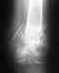

Здравствуйте! Меня зовут Данил, мне 23 года. 7 ноября 2015 года меня сбила машина. Получил перелом левой шейки бедра. Дело было в Санкт-Петербурге и там провели операцию. Вкрутили три винта 11-ого ноября.

Приехал домой в Пятигорск и встал на учёт в травмпункт 1-ого декабря. Заживление прошло нормально. Через месяц уже образовалась хорошая костная мозоль, а через еще где-то месяц мне разрешили давать постепенную опору на левую ногу (срок очень маленький с момента перелома, но я только позже узнал, что такая методика "вставай и иди").

15 марта пошел опять к травматологу. Был дискомфорт при ходьбе. Снимки показали, что образовалась трещина в районе перелома и хирург напугал меня образованием ложного сустава и возможной заменой искусственным. Большинство врачей, у которых был, прописывают строгий пастельный режим в районе 1,5-2 месяца. Еще пью Кальций Сандоз и прошел курс инъекций Миакальцик Кальцитонин. Меня беспокоит, что трещина зарасти не сможет сама по себе при том, что даже лежа я могу беспокоить бедро и сам перелом.

Хочу обратиться ко всем за советами или наставлениями! ЧТО ДЕЛАТЬ?!?!?!Можно ли как то ускорить заживление? Может как то возможно гипс наложить, чтобы стянуть трещину? Может я ошибаюсь, и она сама по себе заживет? Прикрепляю крайний рентген. Буду признателен за любого рода совет!!!

Здесь нужно сделать межвертельную вальгизирующую остеотомию. Вряд ли в Пятигорске эти операции на потоке.